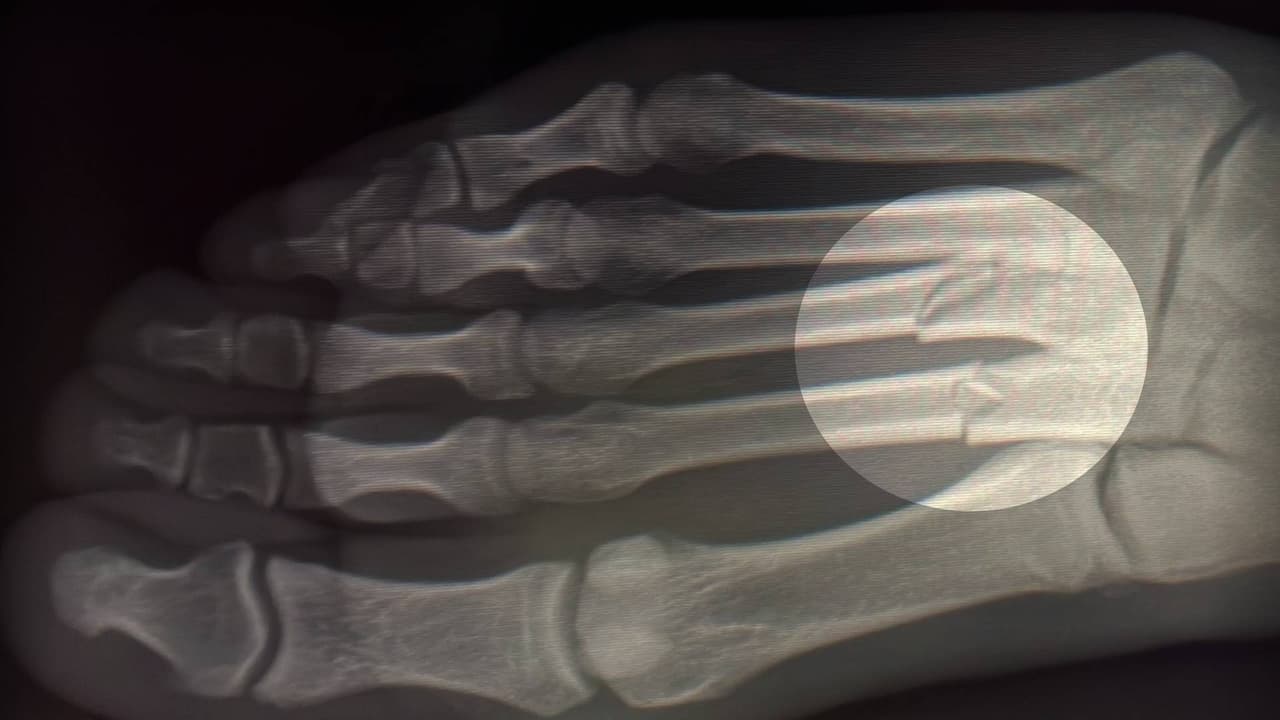

El jugador del Cádiz compartió en twitter la foto de la herida en su pie tras el partido, pero también la radiografía donde se puede apreciar el daño en el que existe fractura desplazada en dos metatarsianos de su pie derecho.

Esto no es bien recibido por los aficionados del Cádiz, pues no sólo tuvo que dejar el partido, sino que tuvo una doble fractura de dos metatarsianos del pie derecho, por lo que será una baja sensible para el equipo.